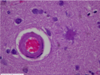

nml neuron

nissl bodies, nml neurons